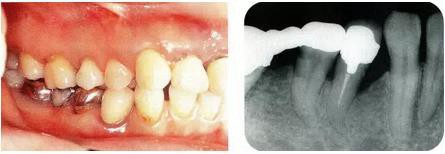

圖17-4(左),5 (右)  術(shù)后9年的口腔內(nèi)照片和X線片,牙槽嵴平坦化,牙周探診數(shù)值很小。